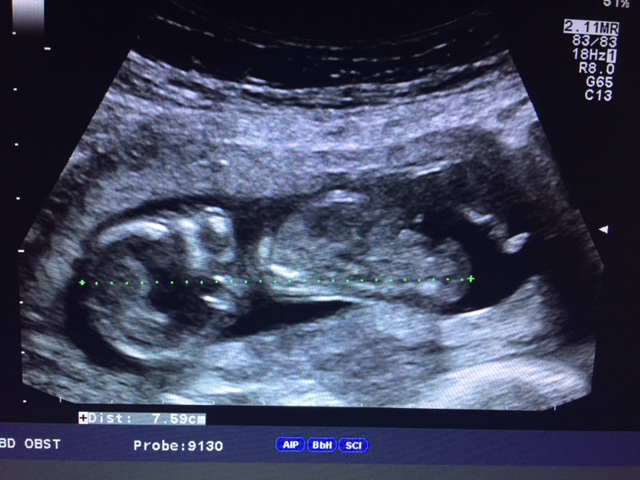

Her long legs hihi

Attachment 28840